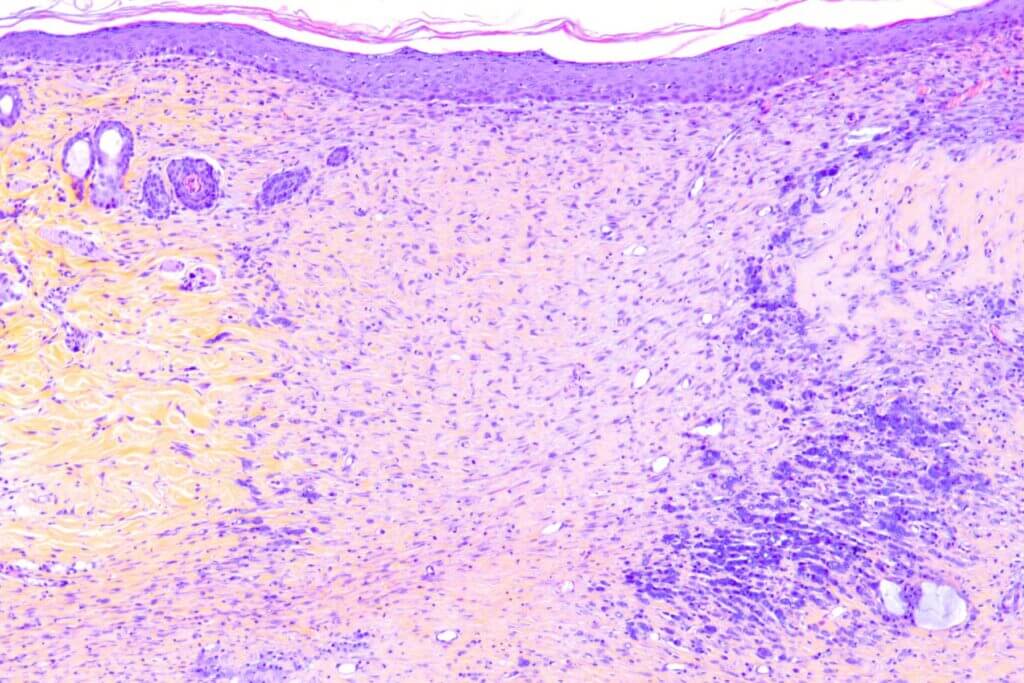

Atopic Dermatitis- DNCB model

Repeated topical applications of DNCB in mice progressively induce inflammation (erythema), edema, erosion, and desquamation, modeling atopic dermatitis. This model includes in situ measurements (TEWL and scoring), behavioral assessments, serum biomarker analyses (IL-33, IgE, histamine…), and histology/immunohistochemistry. It offers high predictive value for clinical success and constitutes a robust tool to evaluate therapeutic efficacy.